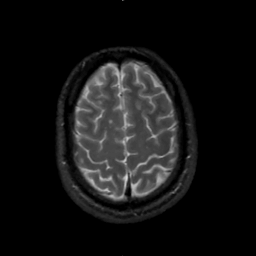

MR Study #1, February 10, 1991 -- Slice #41

[Home][Help][Clinical][Tour 1][Tour 2] Slice 41